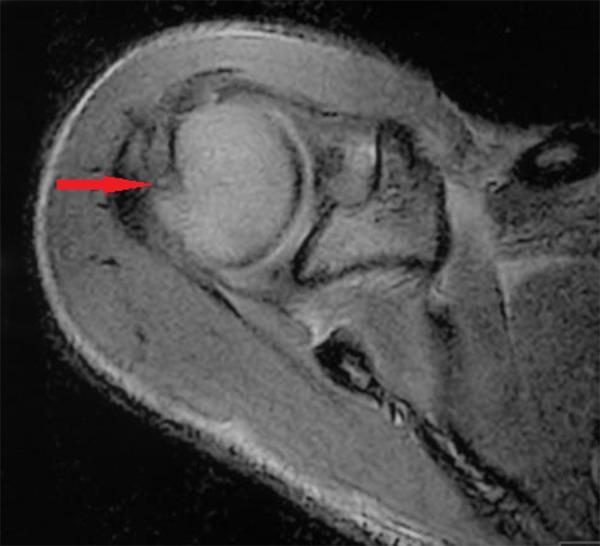

Sports health orthopaedic magnetic resonance imaging challenge: shoulder pain from a fall while surfing.

Begly John P, Wild Aaron T, Garzon-Muvdi Juan, Carrino John A, McFarland Edward G

Sports Health. 2012 May;4(3):261-3. doi: 10.1177/1941738112438040.